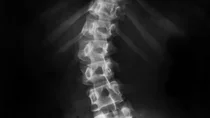

Skoliose: das schwarz-grau-weiße Röntgenbild einer Wirbelsäule Skoliose: das schwarz-grau-weiße Röntgenbild einer Wirbelsäule

Skolyoz nedir?

Ergenlikte skolyozda omurga eğrilir ve döner. Hastalık belirgin bir sebep olmadan gelişir. Bu nedenle "idiyopatik" olarak da adlandırılır (Yunanca idios: "kendi" ve pathos: "acı çekmek" kelimelerinden sonra). Skolyoz neredeyse sadece büyüme sırasında gelişir.

Skolyozda omurga farklı derecelerde eğri olabilir. Eğrilik derecesi Cobb açısı olarak bilinir ve bir röntgen filmiyle belirlenir.